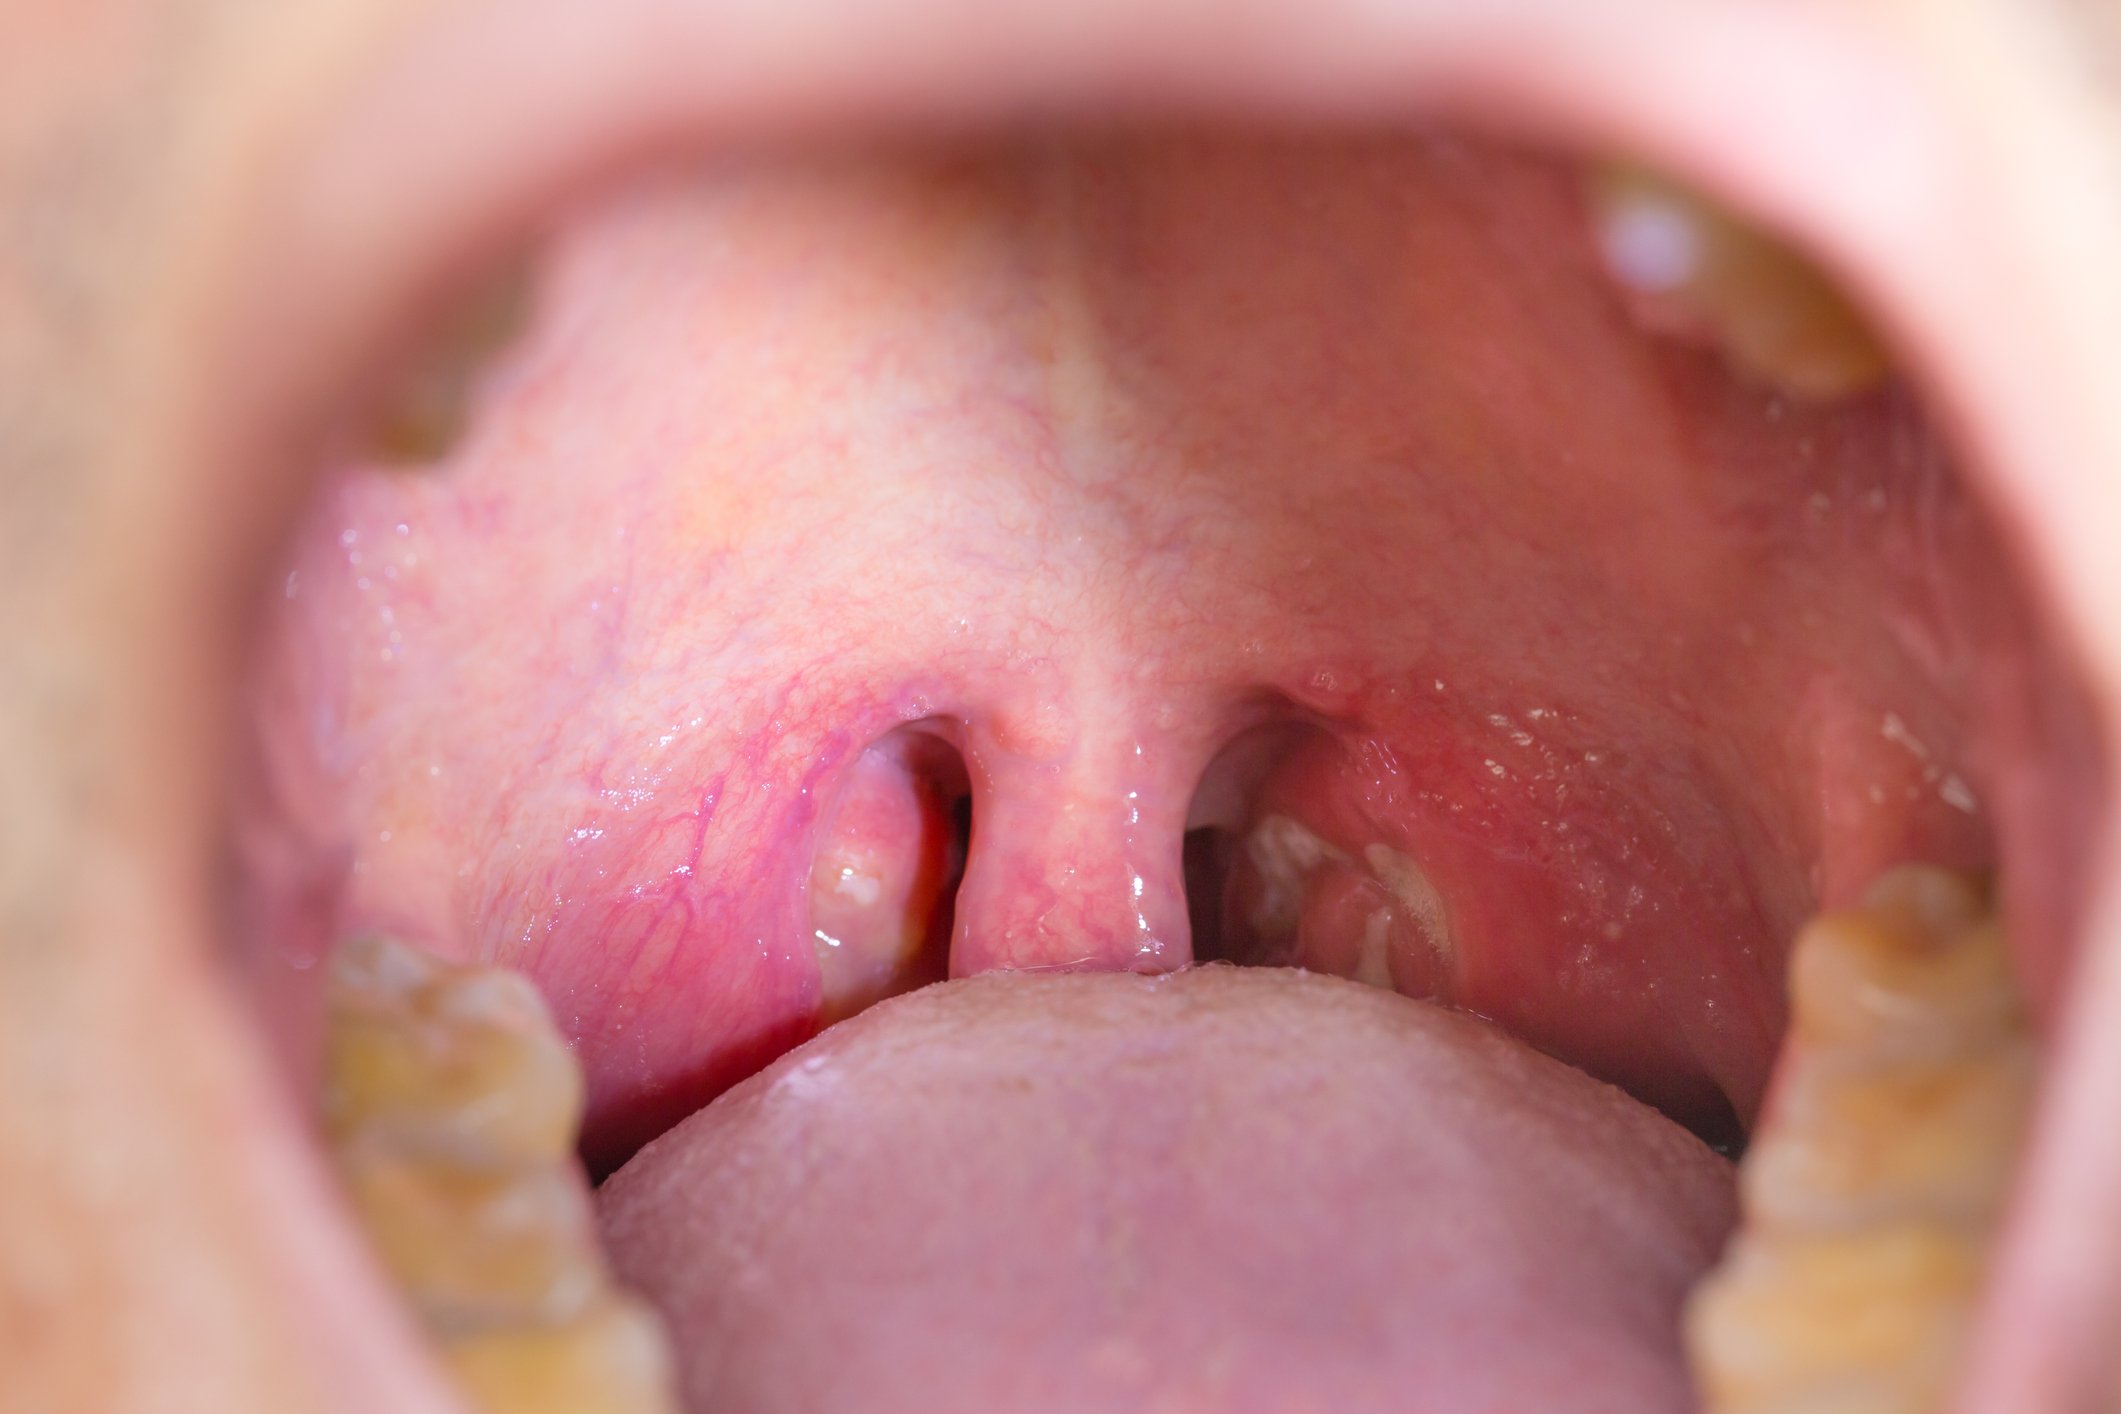

Generally, children that are prone to contracting throat infections and have a difficult time breathing at night because of swollen tonsils are the typical entrants. While tonsillectomies can help to breathe during sleep and may reduce the frequency of throat infections in the short-term, Australian researchers found that the removal of tonsils or adenoids in the throat also increased the chances of allergic conditions and skin and eye diseases as well.

It is believed that this is because these tissues play a more important role that may have been previously thought by detecting and blocking the invasion of bacteria and viruses from getting into the lungs and throat.

The removal of the adenoids — the tissue at the back of the roof of your mouth right under the nasal cavity actually doubled the risk of chronic pulmonary disease, which includes asthma and emphysema. These conditions are much rarer than typical respiratory infections, only 0.25 percent of the general population in their 30’s has a form of COPD.

Authors of the study concluded that it was “not surprising” that removing these key parts of the bodies immune system might make one more susceptible to contracting a respiratory or immune-related illness or disease. Heightened susceptibility to 28 forms of the disease, which included skin diseases, eye infections, and parasitic infections. These diseases were 78 percent more prevalent in people who had previously had these surgeries.

Because the aforementioned diseases are unrelated to the airways it goes to show that there is a greater function to the role of the tonsils than previously thought.